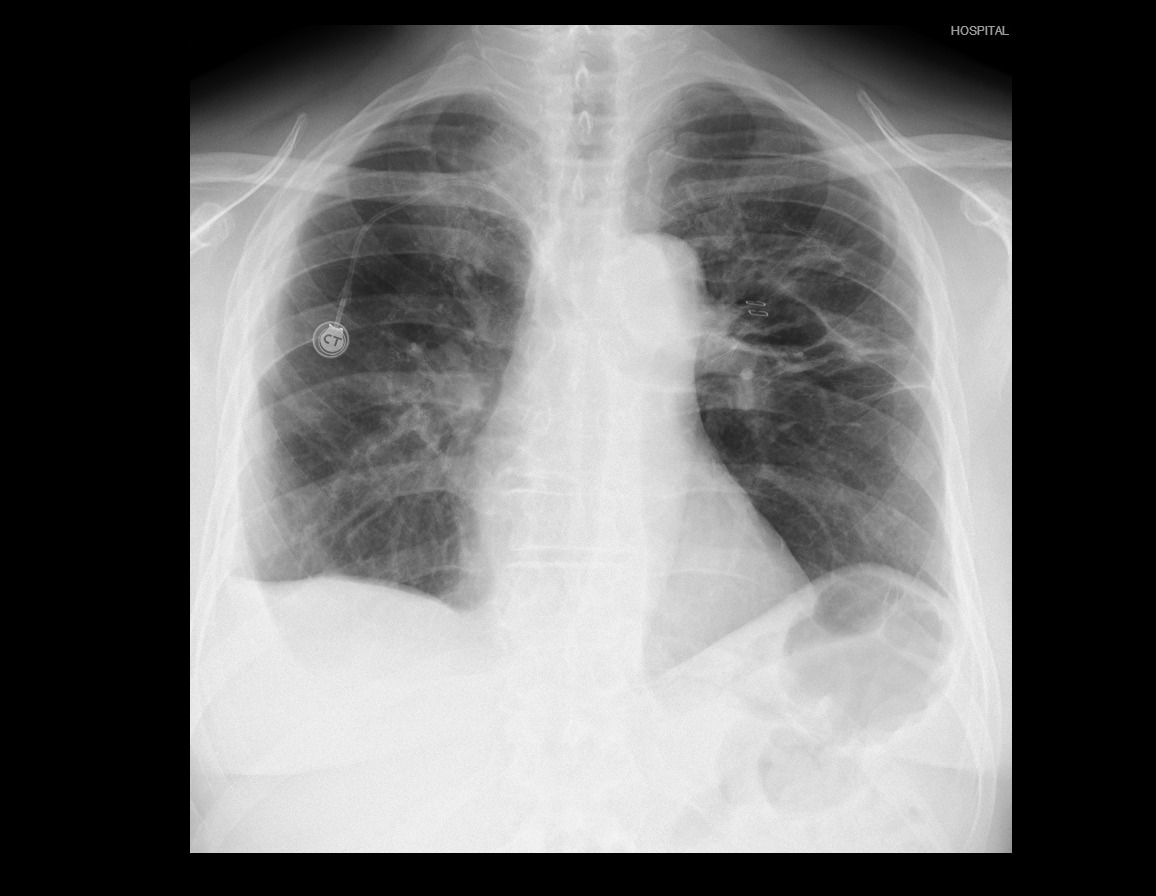

There was no postoperative air leak, and the right chest tube was removed 48 hours after the surgery. The patient’s pain visual analogue scale scores were 3 and 2 at 24 and 48 hours after surgery. A contralateral empyema in the middle posterior pleural space due to bronchopleural fistula and the valve placement was diagnosed postoperatively. It was successfully managed with wide-spectrum antibiotic therapy and ultrasound-guided drainage. The patient was discharged on the 8th postoperative day with satisfactory chest X-ray (Figure 2). The final pathology report demonstrated a 2 cm intestinal metastasis with free bronchial, vascular, and fissural margins. The patient continues follow-up with medical oncology.

Figure 2